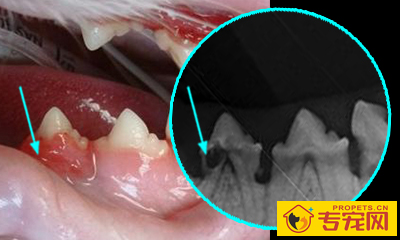

这些操作都是需要麻醉进行外科手术的,狗狗们在麻醉状态下,兽医会给他们拍摄牙科x光片,仔细检查每一颗牙齿的情况,判断是否要拔牙或是保留。

牙周病引起口臭最常见的原因是由牙菌斑引起的牙周病。刷牙后数小时内,牙菌斑就会重新附着到牙齿表面。几天之内,牙菌斑就会矿化,产生牙结石。牙菌斑和牙结石中的细菌会产生硫化氢导致口臭。